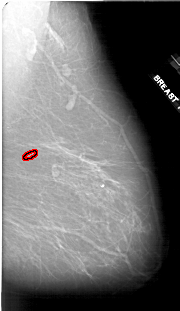

A_1910_1.LEFT_MLO

LEFT_MLO LINES 6466 PIXELS_PER_LINE 4006 BITS_PER_PIXEL 12 RESOLUTION 43.5 NON_OVERLAY